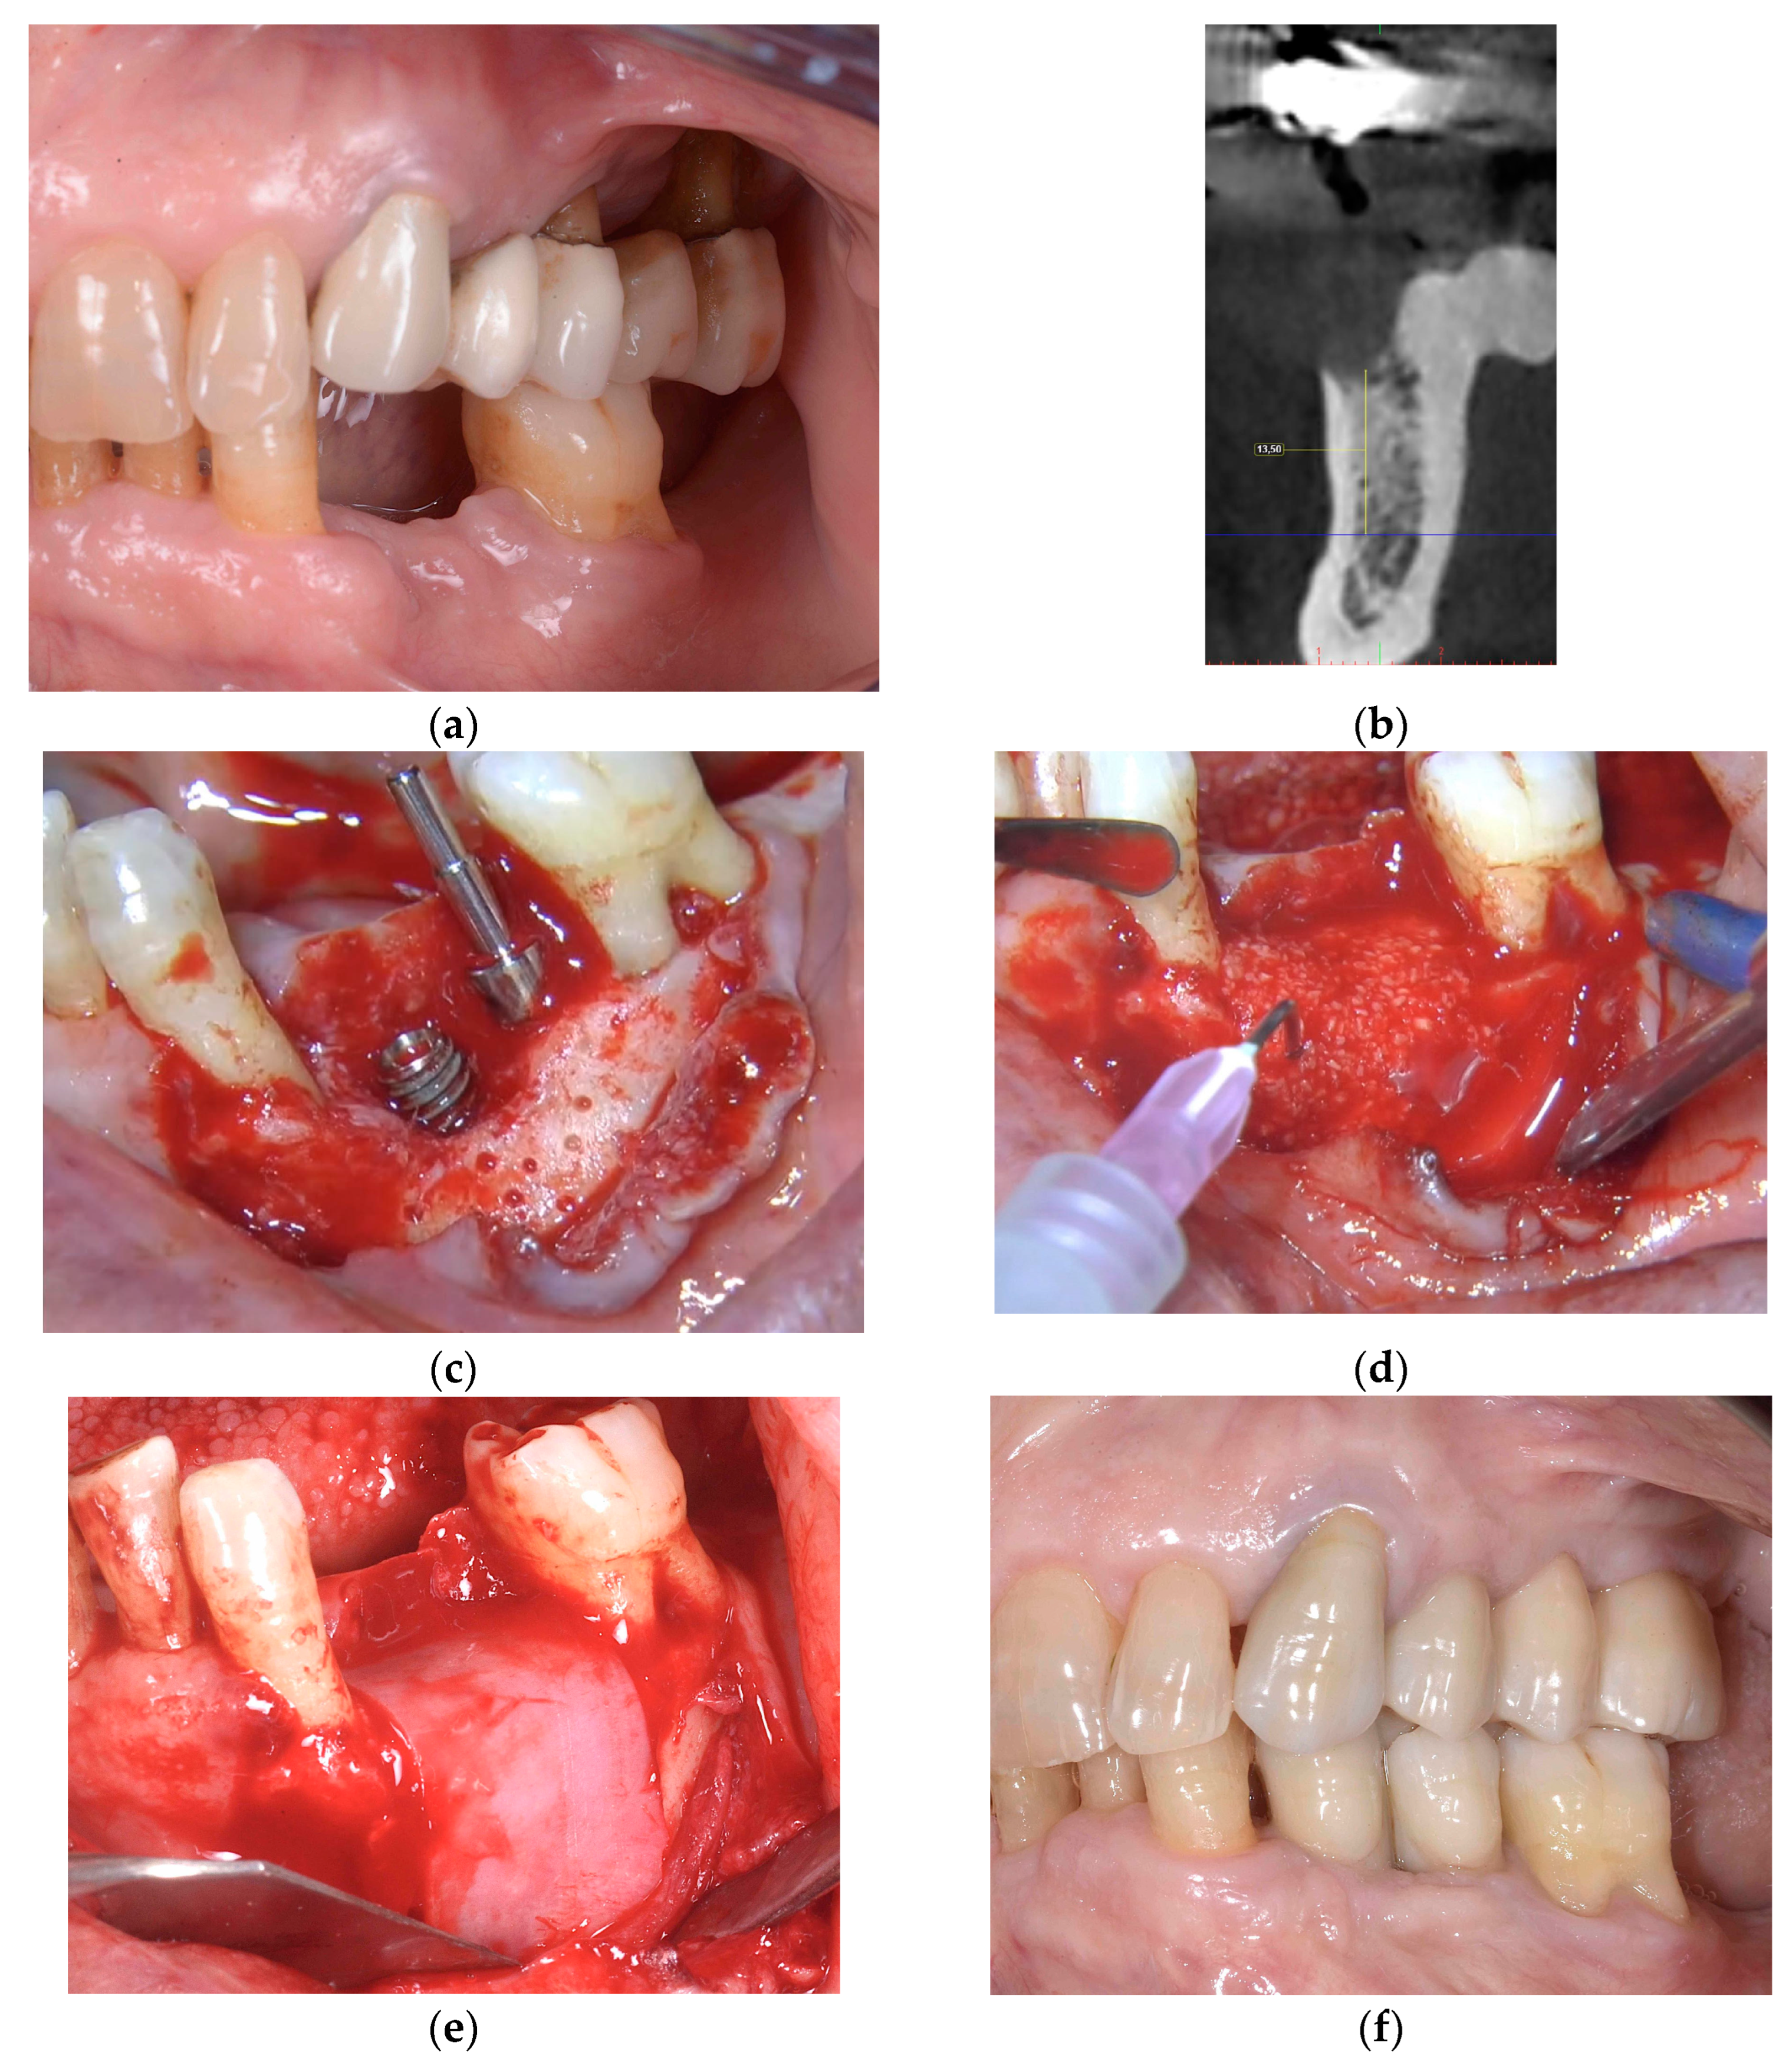

2.2.1. Horizontal and Vertical GBR Using F.I.R.S.T.

2.2.2. Immediate Implant Placement Using F.I.R.S.T.

2.2.3. ARP and Delayed Implant Placement Using F.I.R.S.T.

- Foti, V.; Rossi, R. Fibrinogen-induced regeneration sealing technique (first) an improvement and modification of traditional gbr: A report of two cases. Mod. Res. Dent. 2020, 5, 476–485. [Google Scholar]

- Foti, V.; Savio, D.; Rossi, R. One-time cortical lamina: A new technique for horizontal ridge augmentation. A Case Ser. Br. J. Healthc. Med. Res. 2021, 8, 22–30. [Google Scholar] [CrossRef]

- Foti, V. Fibrinogen-induced regeneration sealing technique (f.I.R.S.T.). In Building Better Bone: A Comprehensive Guide to gbr Techniques; Rossi, R., Ed.; Quintessence Publishing: Batavia, IL, USA, 2024; pp. 210–227. [Google Scholar]

- Faro, L.L.; Strappa, E.M.; Carù, F.G.; Nanni, M.; Invernizzi, M.; Testori, T. Rigenerazione ossea guidata con tecnica first (fibrin-induced regeneration sealing technique). Case report con evidenze istologiche. Quintessenza Internazionale Riv. Di Odontoiatr. 2023, 37, 10–21. [Google Scholar]